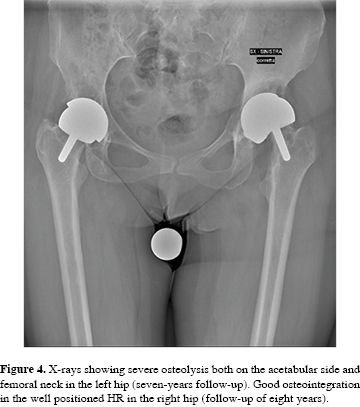

Annually scheduled follow-up for clinical and radiographical examinations showed excellent outcome until April 2011, when the patient started complaining of groin pain on the left side (HHS was 64). Radiographs showed severe osteolysis of both the acetabular and femoral sides with extensive neck narrowing (Figura 4).

Revision surgery was performed in June 2012 and a stemmed THA with modular dual mobility (MDM) system (ceramical 28-mm femoral head, 60-mm acetabular cup, metal insert and a 48-mm UHMWPE liner) (Stryker, Michigan, USA) was implanted. A good implant stability was achieved using autologous bone graft and two screws (Figura 5).